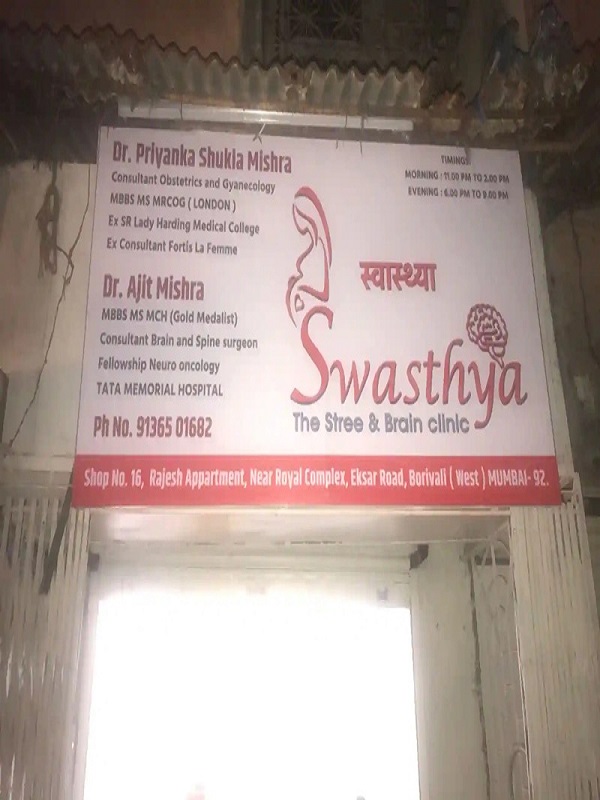

Mumbai Neuro Care, is a Neuro Multispeciality clinic, based at Mumbai, Maharastra.

Dr. Ajit Mishra is Neurosurgeon with Gold Medalist. He is practicing over 5 years of experience in Swasthya-The Street & Brain Clinic. Dr. Ajit had his education in MBBS, MS, MCh Neurosurgeon in NIHANS with Gold Medal. He is a fellowship Neurosurgical oncology in Tata Memorial Hospital, Mumbai. His special interest in Brain and Spine tumor, stroke , Head injury ( Trauma ) , endoscopic surgery & more.

Mumbai Neuro Care, Mumbai

Sho No 16, Rajesh Appartment, Eksar road, CKP colony

Borivali West, Mumbai, Maharastra, India

drajitm@gmail.com

+91 9136501682, 8108822947